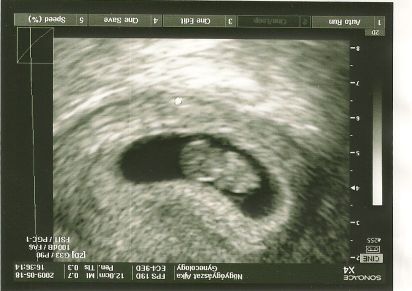

Tulipános! De jó a kép! Az elsőn pont elölről látni, nagyon édes!